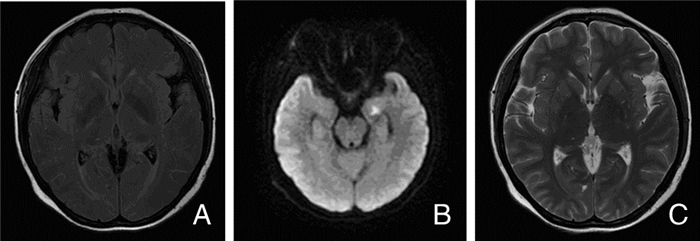

查头颅CT平扫未见异常。头颅MRI+DWI+MRA:右背侧丘脑见小片T1等信号,T2高信号影,DWI呈高信号,边界清,MRA未见异常,考虑右背侧丘脑新发腔隙性脑梗死(图 1)。血常规:WBC:7.06×109/L,Hb:98 g/L,PLT:118×109/L。初步诊断:①脑梗死;②自身免疫性溶血性贫血。予保护神经元、清除自由基及促进侧枝循环建立等治疗。

| 图 1 患者入院时MRI图像 注:A:右背侧丘脑见小片椭圆形DWI高信号影;B:病灶于T1呈等信号;C:MRA未见异常 |